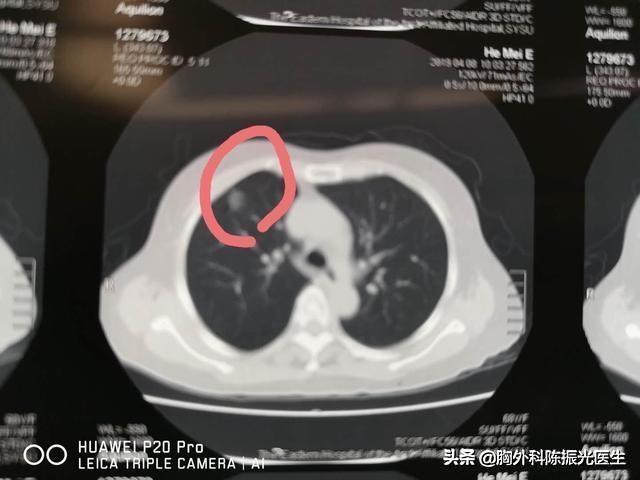

我看了她的片子,8*15mm肺结节,空泡征,长短毛刺,血管集束症。我考虑结节是恶性的可能性比较大,了解到患者身体情况允许,所以建议手术治疗。

肺癌高位结节,如直径≥15mm或表现出恶性CT征象(分页、毛刺、胸膜牵拉、含气细支气管征和小泡征、偏心厚壁空洞)的直径介于8~15mm的肺实性结节、直径≥8mm的部分实性结节短时间内增大,需要医生考虑如何进一步检查明确诊断,以及采取什么方法进行治疗。对于高度怀疑未恶性者且适合外科手术治疗者,首选外科治疗。